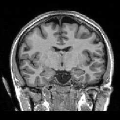

In order to evaluate the impact of such smoothing, classification tests have been conducted based on images reconstructed with both methods. Gray and white matter classification results using the Morphologist 2012 pipeline of -MRI toolbox of Brainvisa software444http://brainvisa.info at and are compared to those obtained without acceleration (i.e. at ), considered as the ground truth. Displayed results in Fig. 2 show that classification errors occur due to reconstruction artifacts for mSENSE, especially at . Results show that the gray matter is better classified using our 3D-UWR-SENSE algorithm especially next to the artifact into the red circle (Fig. 2 []), which lies at the frontier between the white and gray matters. Moreover, reconstruction noise with mSENSE in the centre of the white matter (left red circle in Fig 2 []) also causes miss-classification errors far from the gray/while matter frontier. However, at and classification performance is rather similar for both methods, which confirms the ability of the proposed method to attenuate reconstruction artifacts while keeping classification results unbiased.